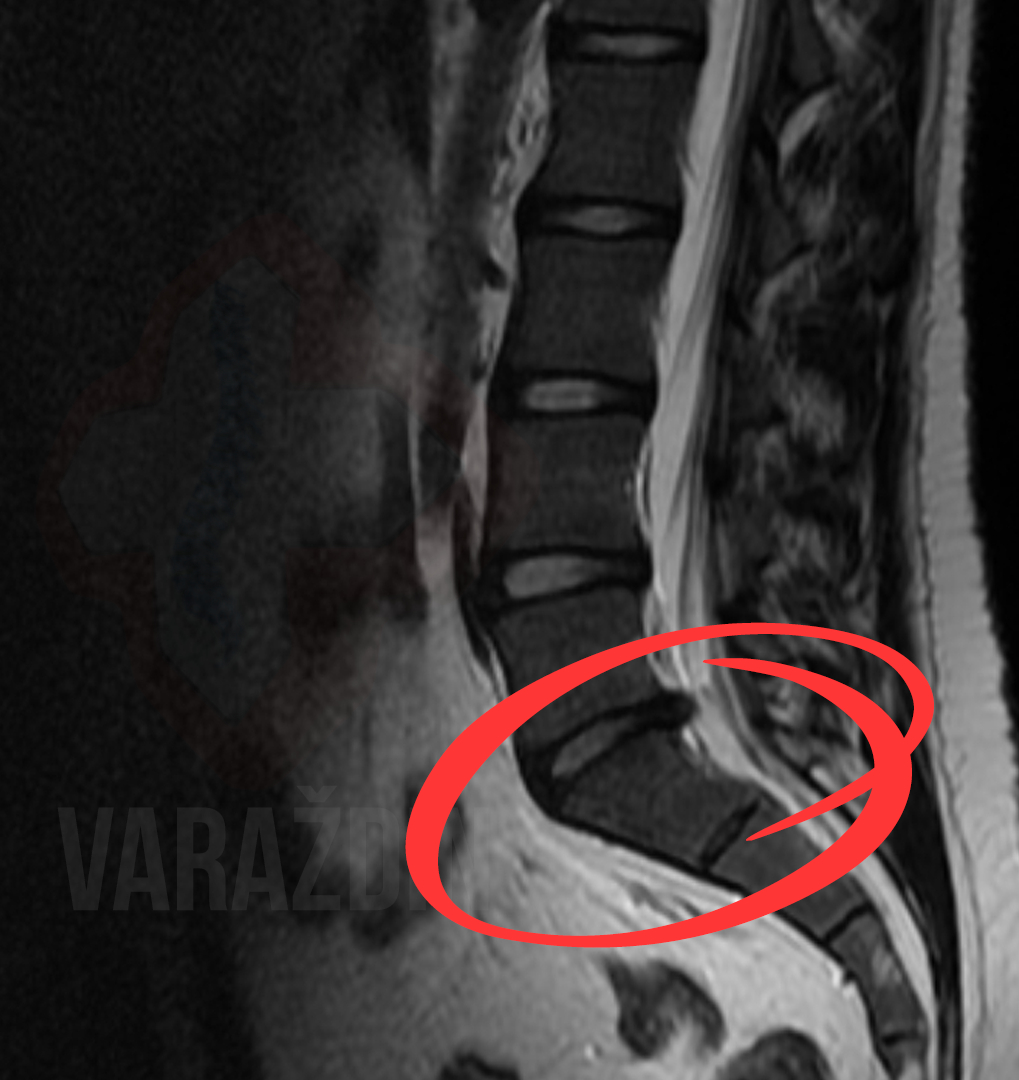

Primjer 5

Klijentica K.A. se javila uz vrlo snažnu bol u lumbalnom području

i lijevoj nozi. Bol je bila toliko jaka da je ležanje bilo moguće

jedino na desnom boku. Preporukom neurokirurga R.S. kreće na

dekompresijske tretmane u Nado centar zdravlja

Varaždin. Dekompresijski tretmani pokazali su se uspješnima,

obzirom da je klijentica nakon 8 tretmana uspješno prespavala

(što je do tada bilo potpuno nemoguće) noć na trbuhu. Rezultate

vidjeti možeti na slikama uz objavu. Hvala na preporuci

neurokirurgu R.S. i ukazanom povjerenju od strane klijentice!